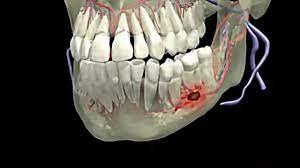

شكل خراج الأسنان في الأشعة

وفيما يخص شكل خراج الأسنان في الأشعة، فإنه يكون هناك بؤرة غامقة في الضرس تظهر في الأشعة السينية التي يجريها الطبيب قبل التدخل بوصف الدواء أو الجراحة، كما يحدد الطبيب من خلال الأشعة مدى انتشار الخراج في الأسنان المجاورة، وهناك مؤشرات تكشف أن المريض يعاني من خراج تكون كالآتي: